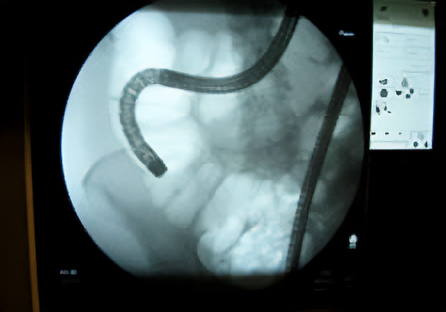

また、内視鏡検査・治療目的のX線透視室も付設されており、処置をはじめとする透視を用いた検査・治療も充分な設備のもとに受けていただけるようになっています。

内視鏡技術と機器の進歩はまさに日進月歩、発見が困難であった小さな病変や、大きな手術が必要であったがんなどの病気も内視鏡検査で発見・治療ができるようになっています。

当院でも様々な内視鏡器具・設備を整え、経験豊富な医師による巧みな技術で適切かつ迅速な診断・治療を行う体制をつくり上げています。

内視鏡器具と技術の進歩により、従来内視鏡では治療が難しかった病気も治せるようになってきています。

当院でも経験豊富な医師により、様々な疾患治療に取り組んでいます。ぜひ一度ご相談ください。